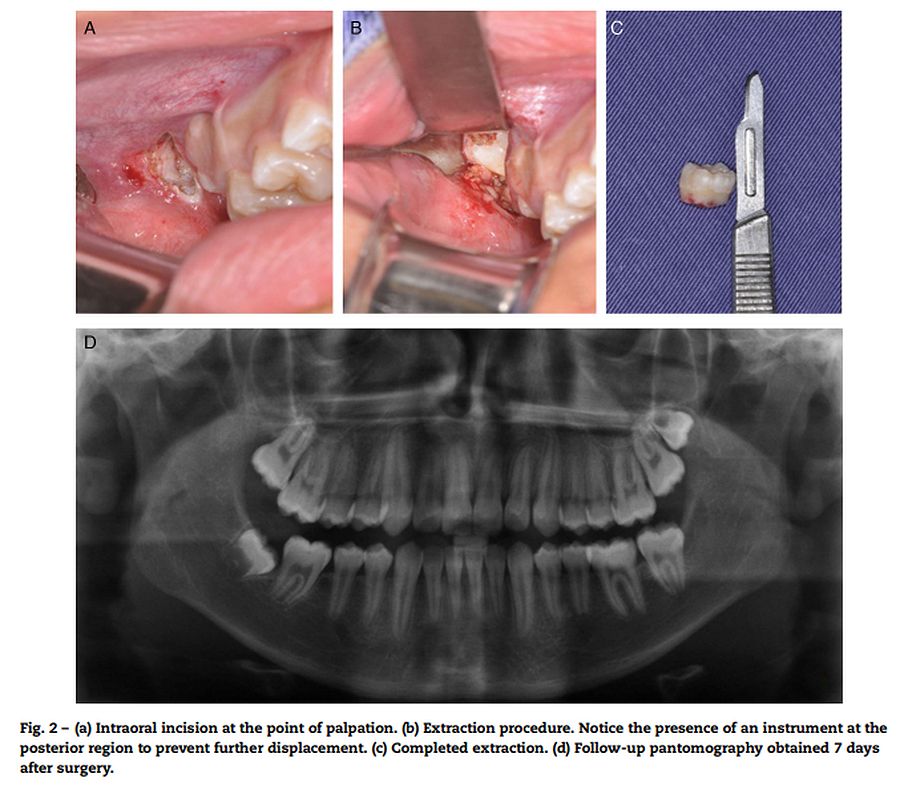

Figure 2 from Iatrogenic fracture of the maxillary tuberosity a case Maxillary Tuberosity Fracture During Third Molar Extraction — the aim of this paper is to enumerate the predisposing and etiological factors of maxillary tuberosity fractures during upper molar extractions, suggest appropriate recommendations, and discuss the procedures that need to be taken when small or large fractured fragments of the tuberosity become evident during surgery. Out of them 73 cases of. This study has the objective of. Maxillary Tuberosity Fracture During Third Molar Extraction.